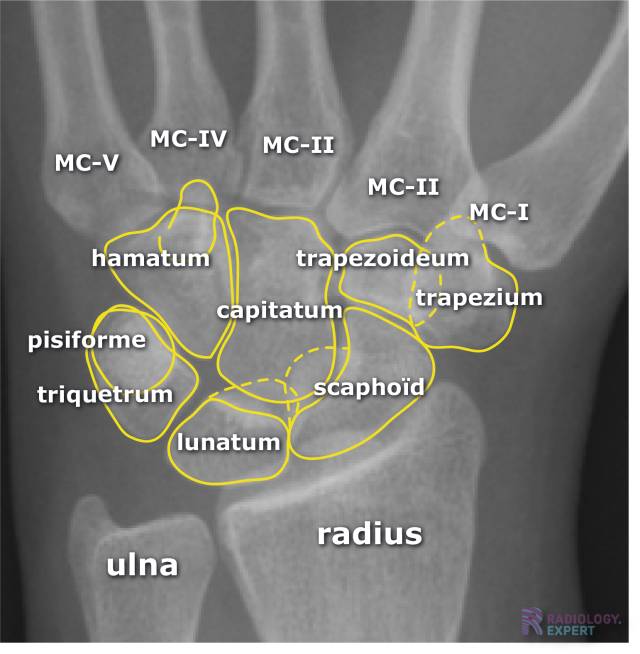

Normale anatomie carpalia. Normale anatomie carpalia.

Klik op afbeelding om overlay te zien